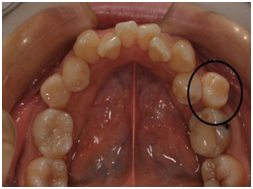

成员三:异位萌出的前磨牙

上图圈出来的牙齿就是这位成员了,他们往往是由替牙障碍引起的。乳磨牙过早脱落,新长出的六龄齿没有了前面的阻挡,逐步向前移动,本该在这个位置上长出来的恒牙被迫从其他位置萌出。对这种情况置之不理,则三颗牙齿之间的间隙会发生食物嵌塞,进而形成龋坏,严重的龋坏会造成三颗牙都无法保留。所以,乳牙发生龋坏后要及时治疗,乳磨牙因无法保留而拔除后也应进行积极的间隙管理,为继承的恒牙留出足够的生长空间。